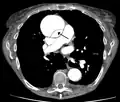

Computed tomography angiography is a fast, non-invasive test that gives an accurate three-dimensional view of the aorta. These images are produced by taking rapid, thin-cut slices of the chest and abdomen, and combining them in the computer to create cross-sectional slices. To delineate the aorta to the accuracy necessary to make the proper diagnosis, an iodinated contrast material is injected into a peripheral vein. Contrast is injected and the scan performed using a bolus tracking method. This type of scan is timed to injection to capture the contrast as it enters the aorta. The scan then follows the contrast as it flows through the vessel. It has a sensitivity of 96 to 100% and a specificity of 96 to 100%. Disadvantages include the need for iodinated contrast material and the inability to diagnose the site of the intimal tear.

-

CT with contrast demonstrating aneurysmal dilation and a dissection of the ascending aorta (type A Stanford) - Chest CT with descending (type B Stanford) aortic dissection (red circle)

Type A dissection with pericardial effusion as a result.